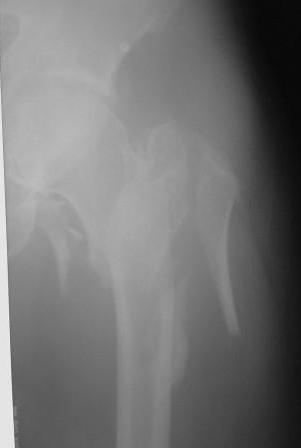

По нашему мнению линия перелома проходит вверху через латеральный отдел шейки бедра, вертельная область состоит из нескольких фрагментов. В таких условиях применить DHS или дистальную бедренную пластину LCP представляется нам сомнительным. Закрытый остеосинтез проксимальным гамма-гвоздем или PFNa невозможен т.к. нет ЭОПа.

Возможно открытый остеосинтез гвоздем PFNa?

Прилагаю Р-ы на вытяжении.